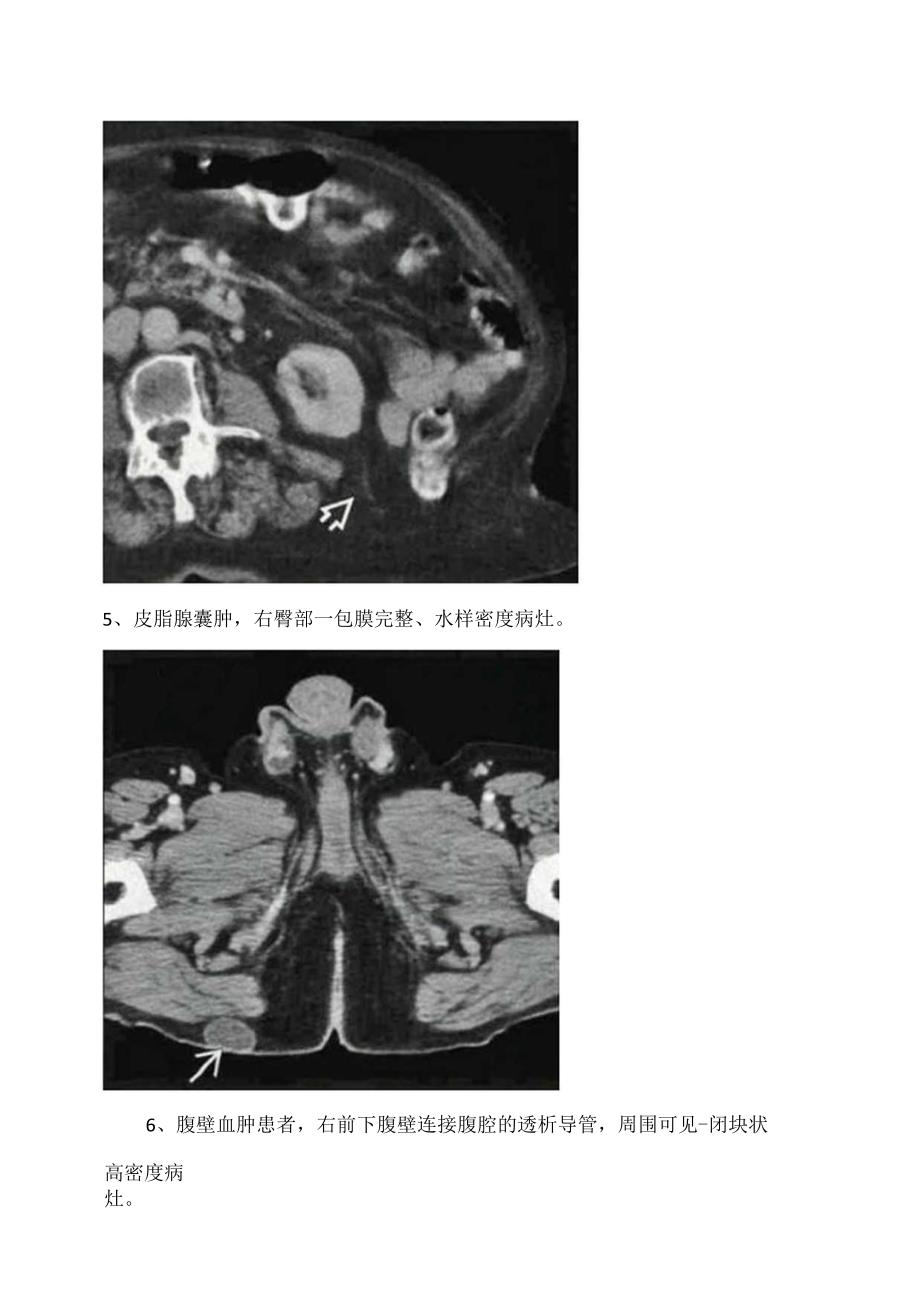

1、临床腹股沟疝、半月线疝、股疝等腹壁病变影像学CT表现1、腹股沟疝,右侧股管前方的疝囊,囊内可见含造影剂的小肠疝入,股静脉未见受压。2、半月线疝(斯皮格尔疝),结肠经左侧腹直肌旁的腹壁缺口疝出,贴附于腹外斜肌前方,疝囊完整。通常疝囊被腹斜肌腱膜覆盖。3、股疝,疝囊位于左侧耻骨结节与股静脉中间,疝入的小肠有梗阻。4、腰疝,CT表现见脂肪和小肠经左能崎附近的胸腰筋膜缺口疝出。5、皮脂腺囊肿,右臀部一包膜完整、水样密度病灶。6、腹壁血肿患者,右前下腹壁连接腹腔的透析导管,周围可见-闭块状高密度病灶。7、r宫内膜异位症,该病例为经历剖腹产的患者,腹壁切口周围一团块状软组织密度病灶,病灶部位周期性疼痛。8